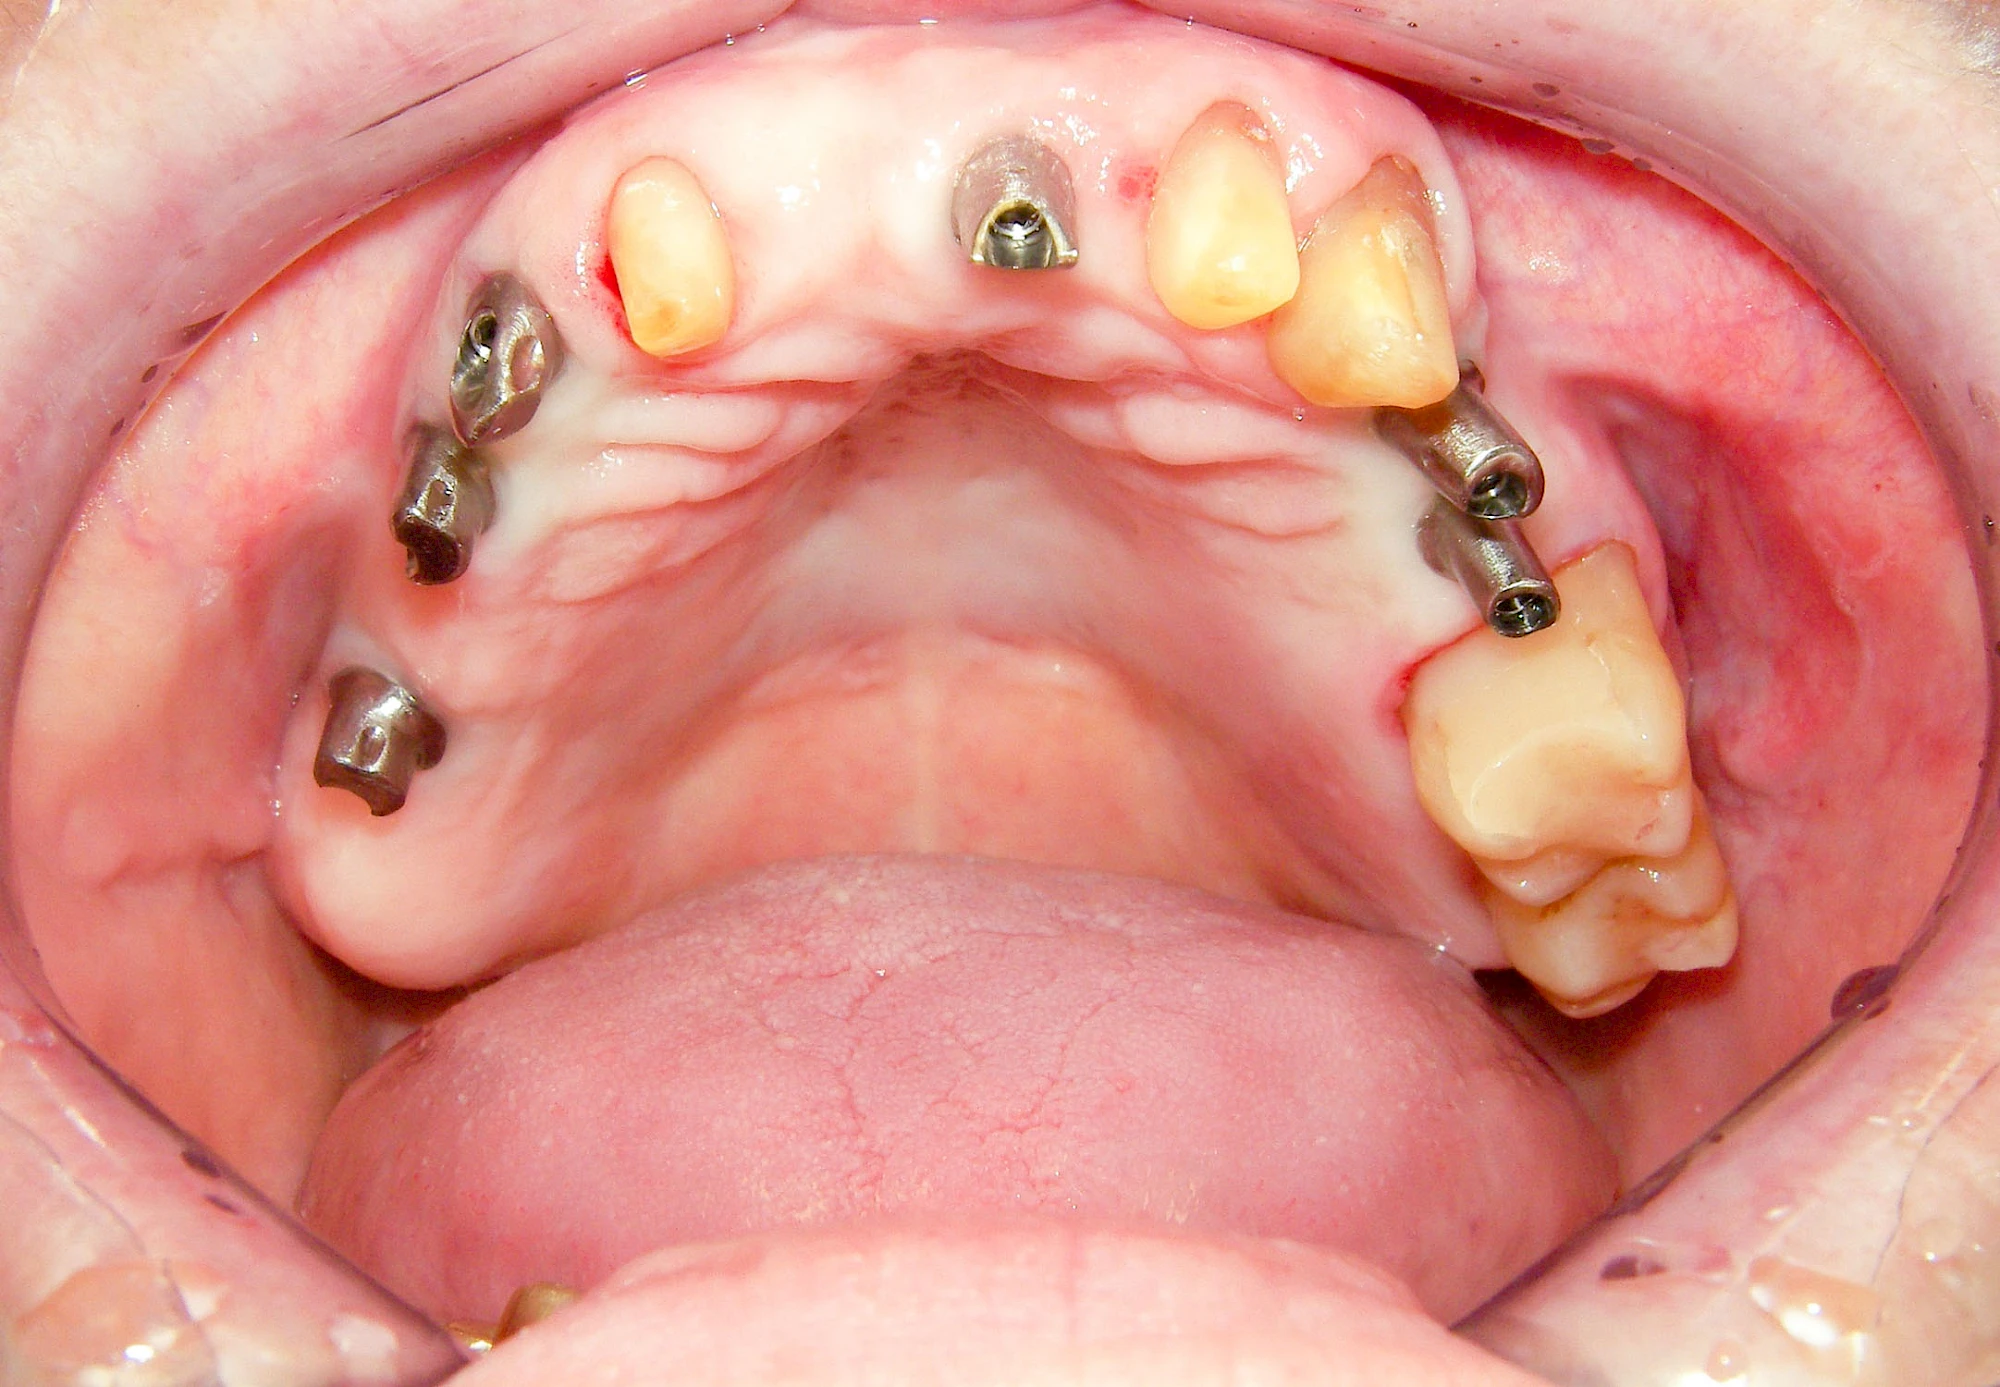

Implantate sind künstliche Zahnwurzeln. Nach einer gewissen Einheilzeit im Knochen (meist 3-6 Monate) erfolgt über einen separaten Aufbau (Abutment) die Befestigung einer Krone bzw. Brücke oder Zahnprothese.

In seltenen Fällen sind Implantate samt Aufbau aus einem Stück gefertigt. Auch gibt es Situationen, die ein Früh- oder sogar eine Sofortbelastung erlauben – dann kann die Einheilzeit der Implantate in den Knochen verkürzt oder sogar gänzlich darauf verzichtet werden.

Fehlen einzelne Zähne und die Nachbarzähne sind unbeschadet oder gut zahnärztlich versorgt, werden immer häufiger Implantate gewählt, um die Lücken zu schließen. Auch bei größeren oder verteilten Lücken, wenn keine herausnehmbare Prothese gewünscht ist, werden Implantate für Kronen- bzw. Brückenversorgungen gesetzt. In Einzelfällen entscheiden sich sogar zahnlose Patienten für eine festsitzende Versorgung auf Implantaten.